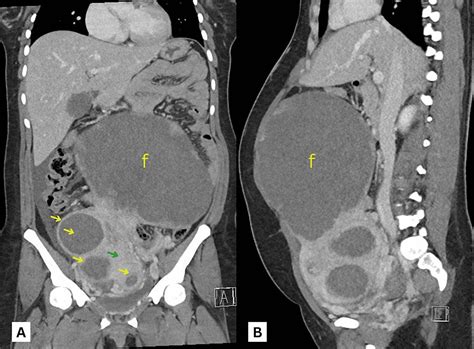

Fibroamele uterine, cunoscute și sub denumirea de leiomioame sau miomuri, sunt tumori benigne ale uterului. Acestea se dezvoltă din peretele muscular al uterului, putând fi localizate la exterior, în interiorul peretelui sau în cavitatea uterină. Fibroamele sunt compuse din țesut conjunctiv (colagen) și apar ca mase dure, albe, cu o structură spiralată.

Leiomioamele uterine reprezintă una dintre cele mai frecvente afecțiuni ginecologice la femei, afectând în special perioada de reproducere. Incidența lor este ridicată, estimată la 70% la femeile albe și peste 80% la cele de origine africană pe parcursul vieții. Fibroamele uterine sunt responsabile pentru un procent semnificativ din internările ginecologice și constituie principala cauză de histerectomie (îndepărtarea uterului).